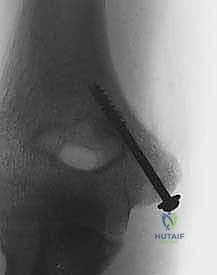

- التثبيت الداخلي (Internal Fixation):

- المسامير (Screws): غالباً ما يتم استخدام مسامير طبية مجوفة (Cannulated Screws) ومجهزة بخيوط جزئية لضغط القطعة المكسورة بقوة ضد العظم الأصلي.

- اختبار الثبات والحركة: قبل إغلاق الجرح، يقوم الدكتور هطيف بتحريك المرفق في جميع الاتجاهات للتأكد من ثبات التثبيت، وعدم وجود أي احتكاك، وتأكيد استعادة نطاق الحركة الكامل.